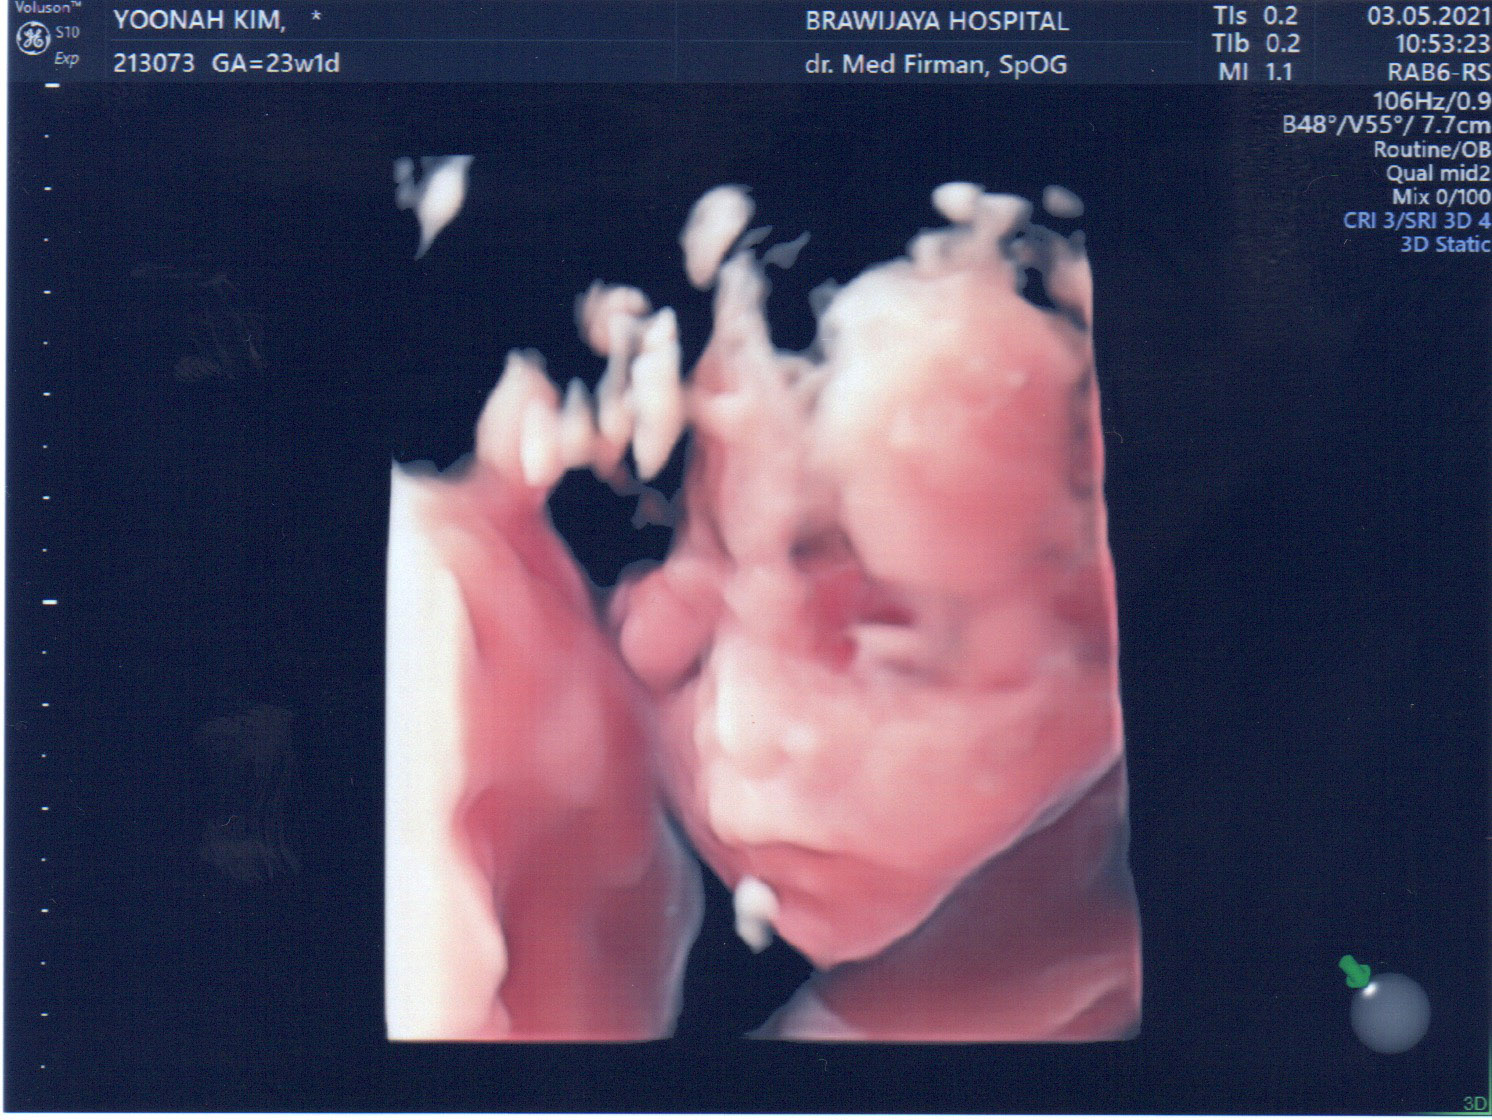

23주만에 드디어 얼굴을 보여주신 울 아드님...

집사람은 코가 낮은 거 같다고 걱정한다. ㅎㅎㅎ

설사 코가 낮다고 하더라도 코가 자랄 시간은 아직 많이 남았다구~~!!